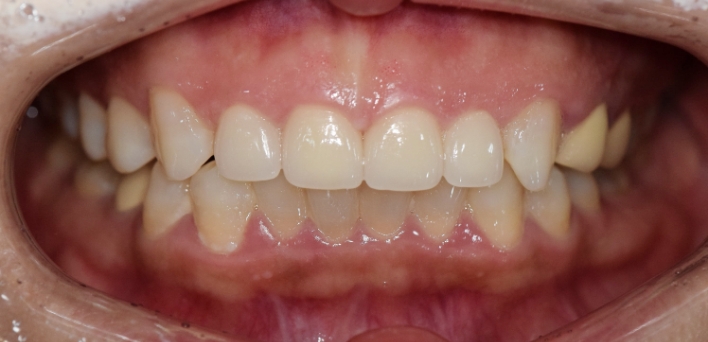

※ 더서울치과의원은 의료법을 준수하며 위 케이스는 실제 환자의 동의를 얻은 사례로 치료 전, 후가 동일한 환경에서 촬영되었습니다.

환자 케이스에 따라 부작용이 발생할 수 있습니다. 이 부분은 의료진의 충분한 상담과 체크를 통해 예방하고 줄일 수 있습니다.

[심미치료 부작용] 시술 후 치아 시림, 보철물 파손 등의 부작용이 발생할 수 있어 개인별 치아 상태에 따른 정확한 진단과 사후 관리가 중요합니다.